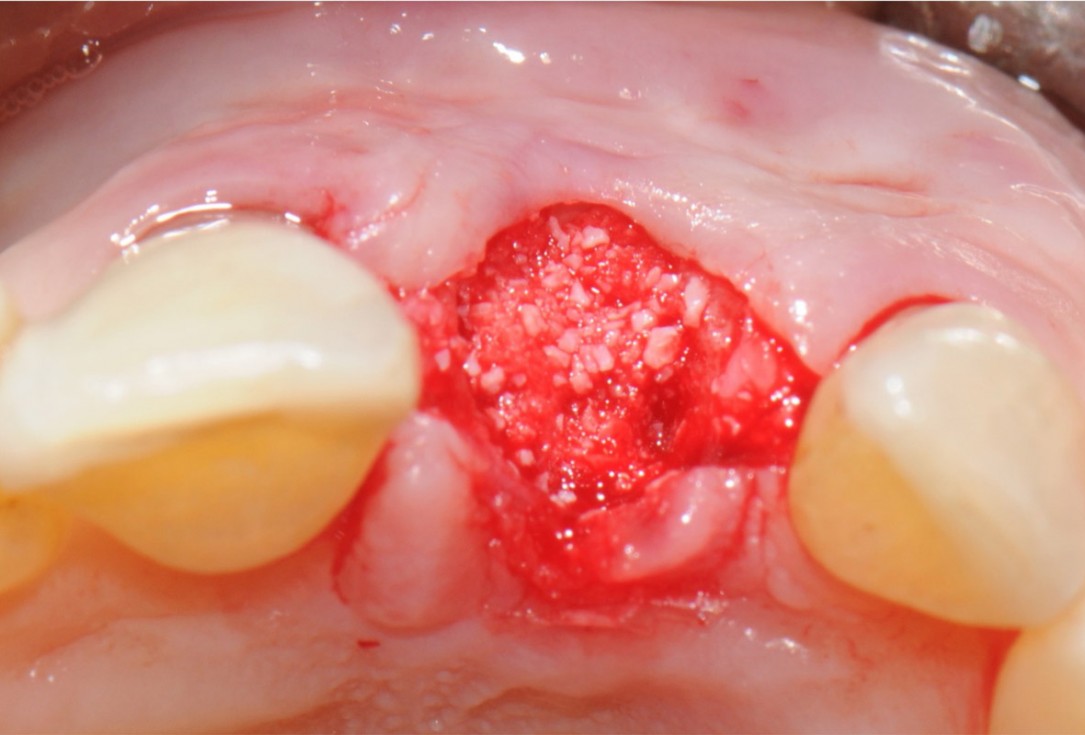

6/18 - Extraction socket filling with bone grafting materialTooth extraction and socket sealing with mucoderm® - Dr. A. Rossi